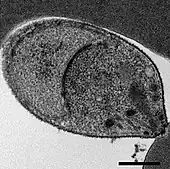

Malaria is traditionally diagnosed by examining Giemsa-stained blood films under a microscope; however, differentiating P. knowlesi from other Plasmodium species in this way is challenging due to their similar appearance.[11] P. knowlesi ring-stage parasites stained with Giemsa resemble P. falciparum ring stages, appearing as a circle with one or two dark dots of chromatin.[17] Older trophozoites appear more dispersed, forming a rectangular-shape spread across the host cell called a "band-form" that resembles the similar stage in P. malariae.[17] During this stage, dots sometimes appear across the host red blood cell, called "Sinton and Mulligans' stippling".[17] Schizonts appear, similarly to other Plasmodium species, as clusters of purple merozoites surrounding a central dark-colored pigment.[17]